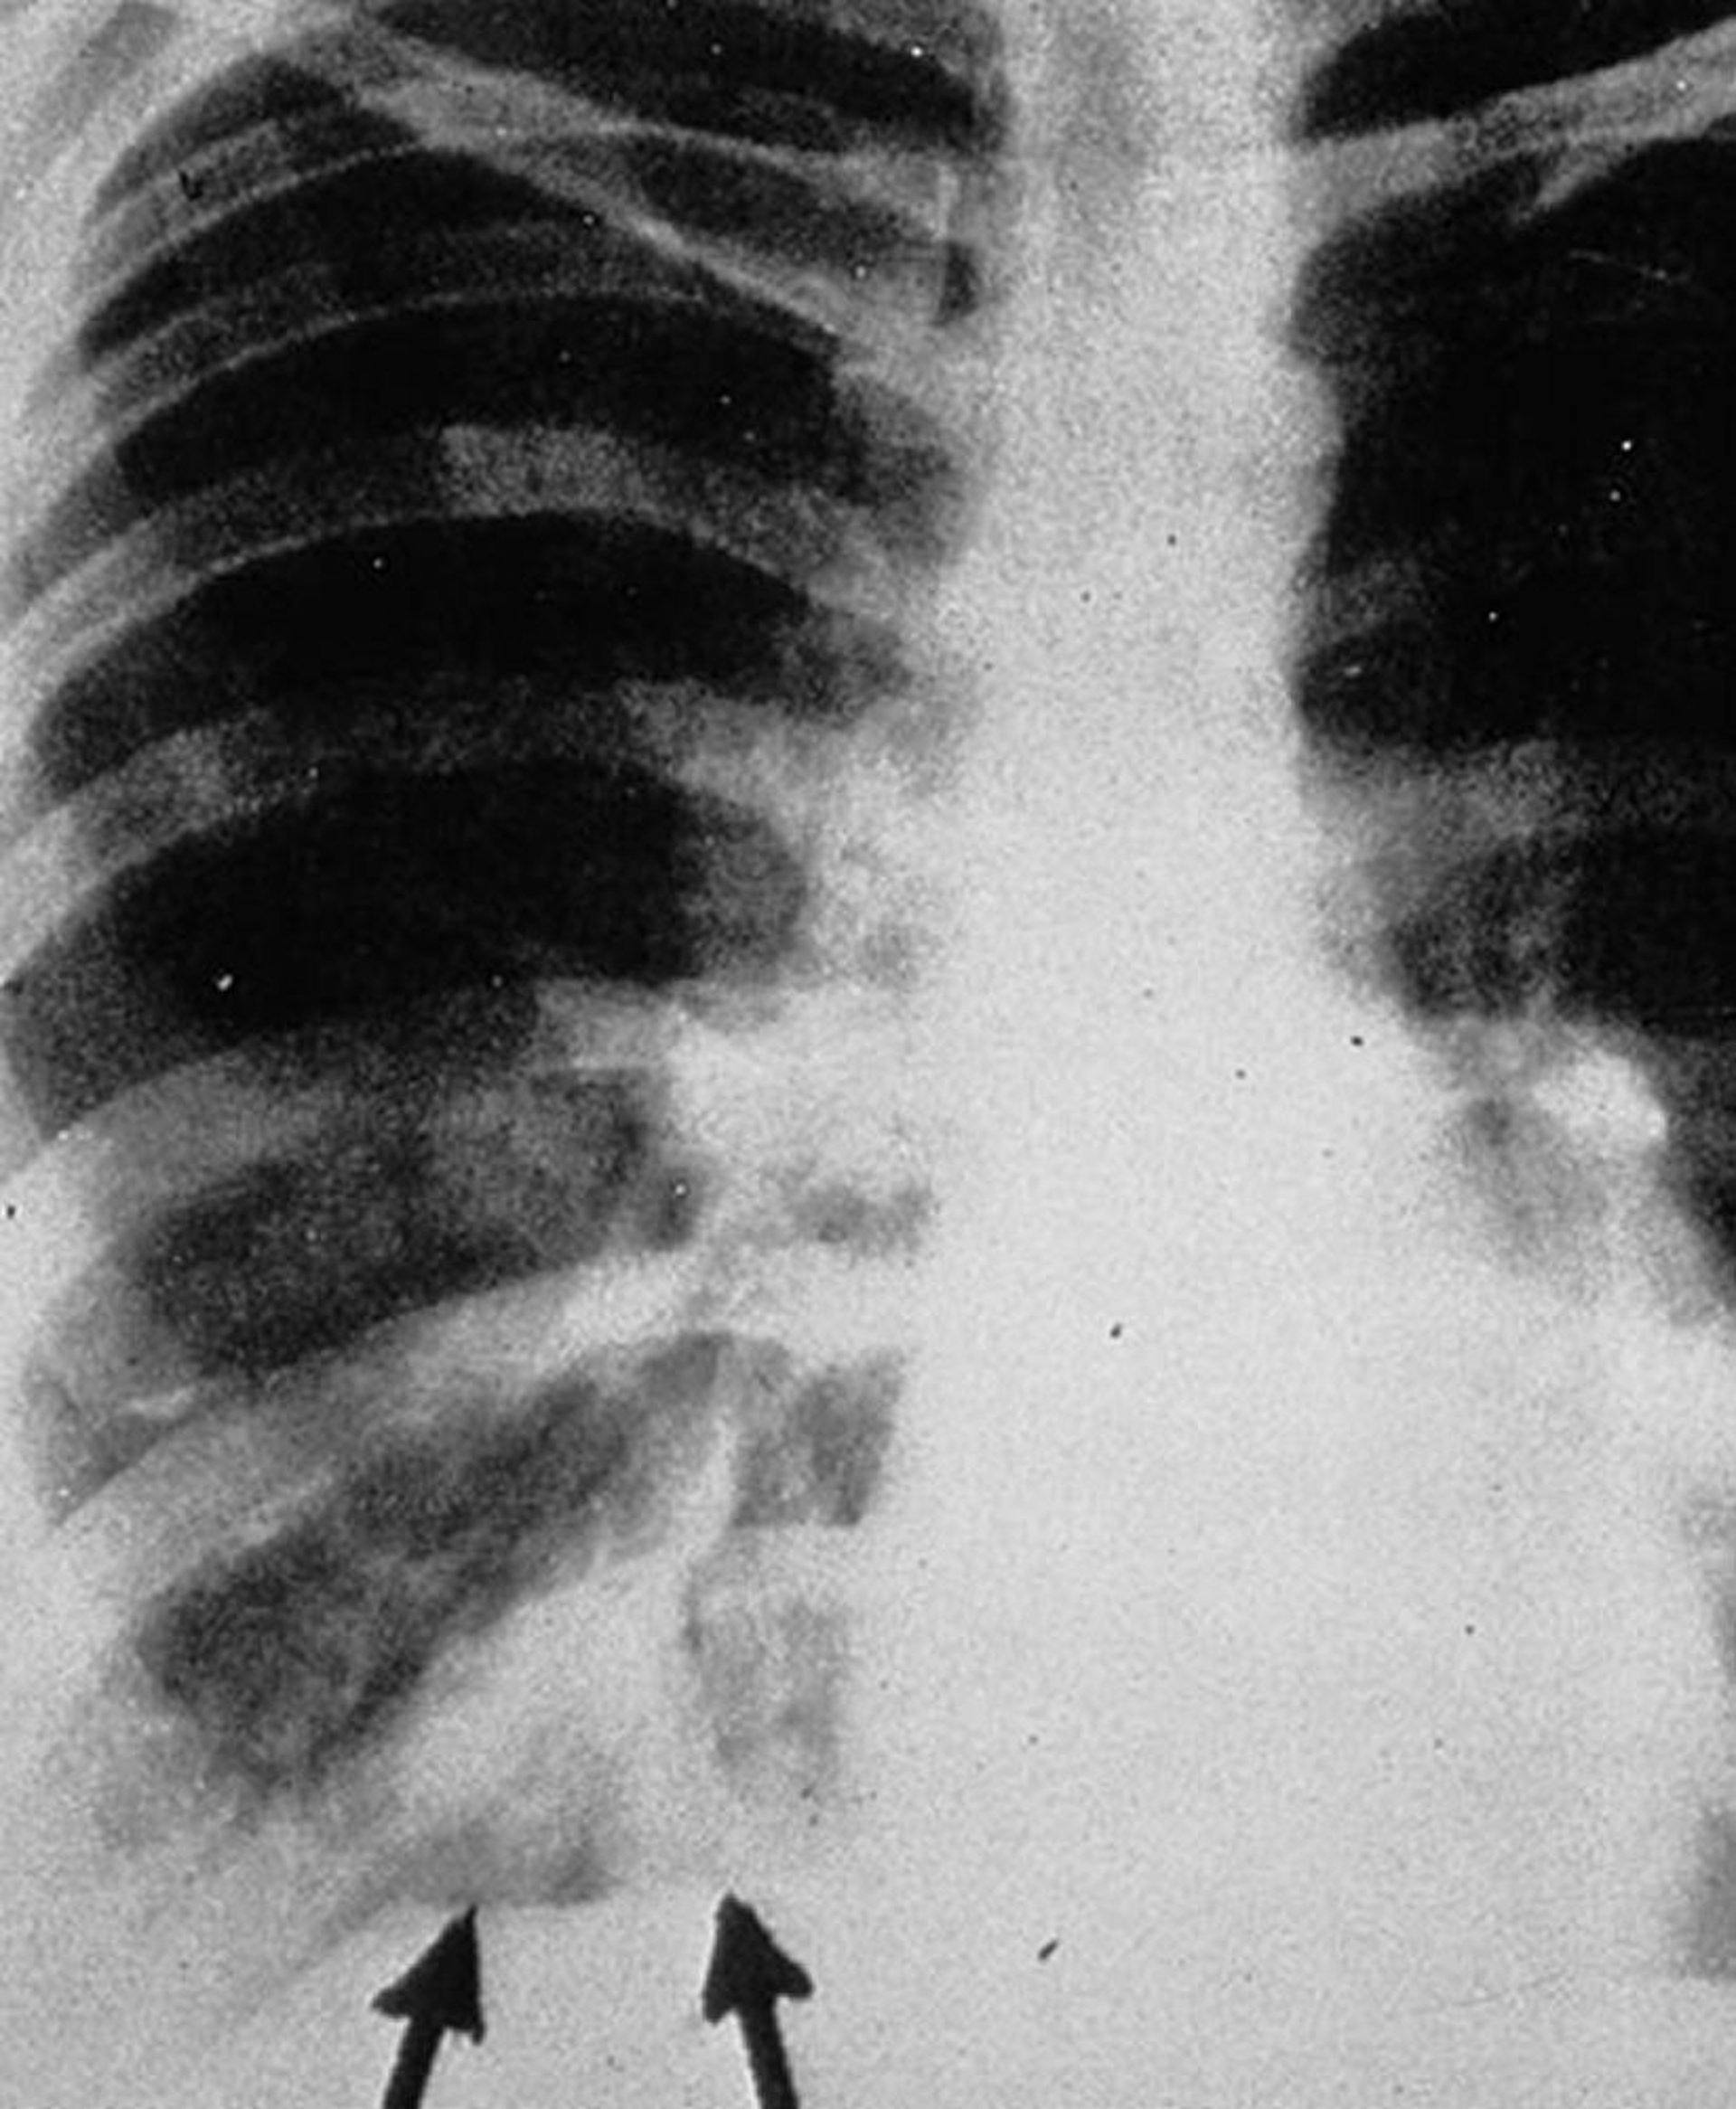

Aspergilosis alérgica o broncopulmonar

La radiografía de tórax posteroanterior muestra sombras tipo "dedo enguantado" (flechas), que aparecen como densidades tubulares ramificadas que representan exudados intrabronquiales con engrosamiento de la pared bronquial.